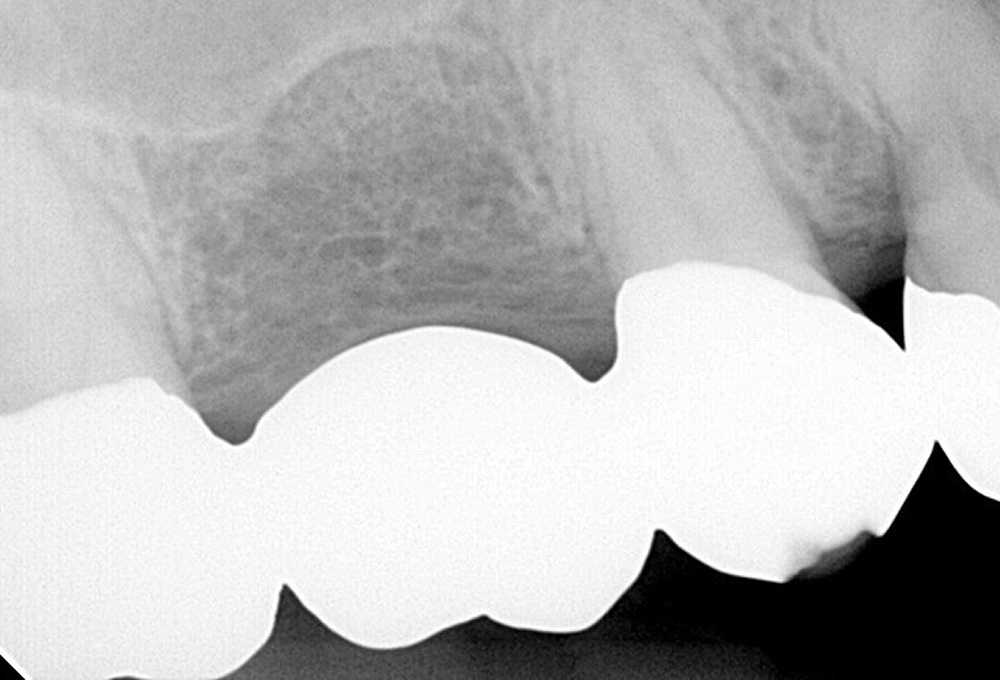

②CTで上顎洞粘膜肥厚 根尖病変確認

③処置後のCT 上顎洞粘膜の肥厚も消失